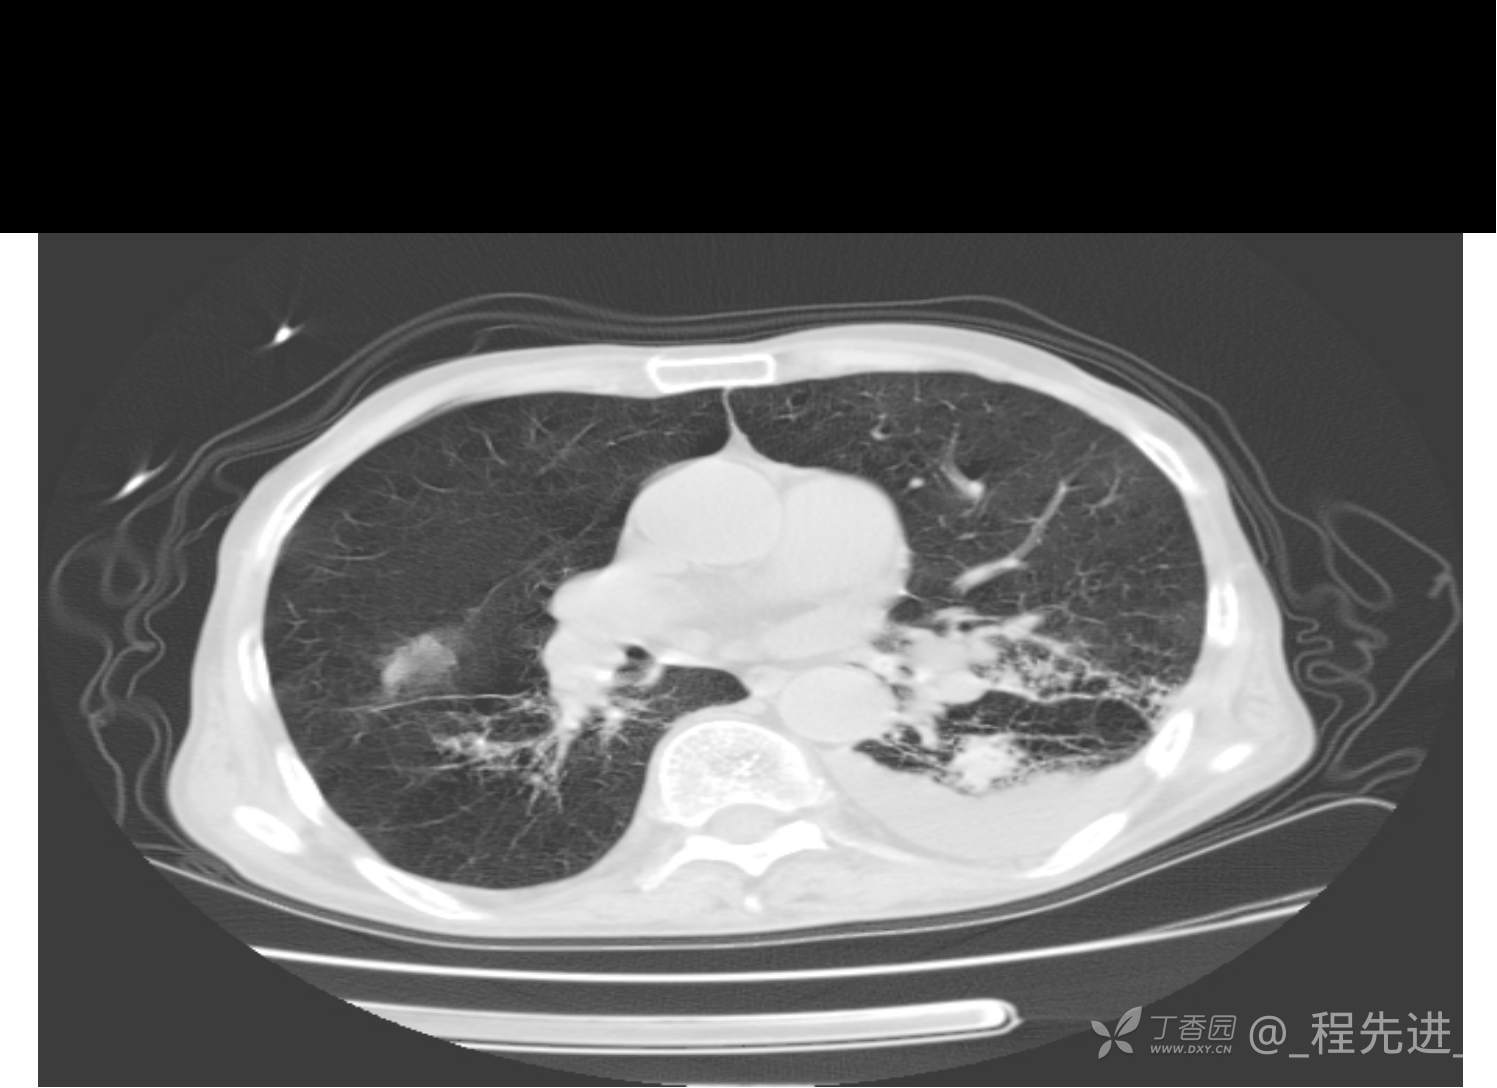

患者性别:男

患者年龄:81岁

简要病史:反复咳嗽、咳痰20余年,加重1周。两肺呼吸音低,可闻及散在干湿啰音。